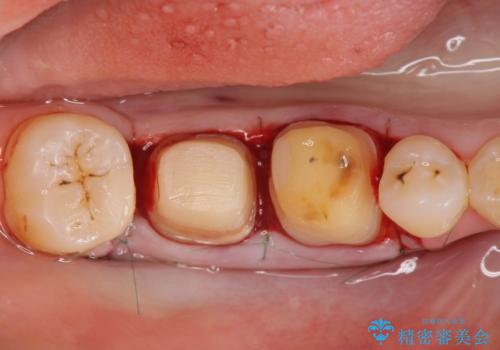

歯周ポケットの除去を併用したセラミック治療

- 歯周病や虫歯、歯の欠けなど多数の問題を他院で指摘され、今後長く持つように歯の問題をしっかりと解決したい。と希望され来院されました。

適合や審美性に優れるセラミック治療を行う前に、歯周病の問題を歯周外科を行うことで解決し将来的に不安のないような口腔内環境を整備していきます。

治療前に4-5mm程度あった歯周ポケットは全て2mm以内となり、非常に清掃性が高く、歯周病の再発しずらい環境に整えた上でのセラミック治療を実践することができました。